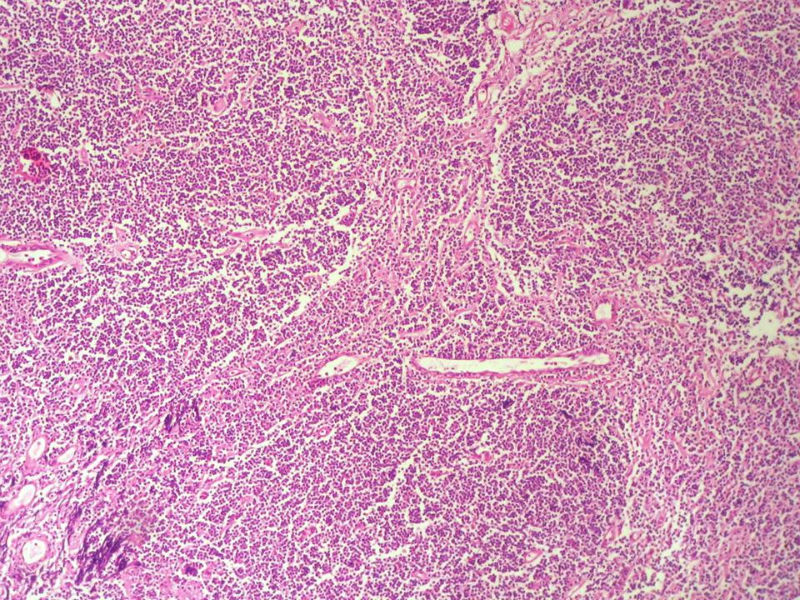

男,49岁,左眼睑球结膜下肿物2个月,手术切除。检查肿块3X2X2厘米,切面灰红色,质软。

淋巴样细胞。细胞形态单一,细胞小。主要鉴别:

1)粘膜相关淋巴组织淋巴瘤

2)小细胞性淋巴瘤/慢性淋巴细胞性白血病

3)套细胞淋巴瘤

形态结构与细胞大小,似不支持滤泡性淋巴瘤。

要多取材,标记鉴别假性淋巴瘤。

请再标记CD20和CD79a!图片中阳性不明确,根据T细胞标记看,应该是B细胞结节。Ki67散而少,不支持低级别滤泡性淋巴瘤,若B细胞弥漫阳性,则是惰性B细胞非霍奇金淋巴瘤,首先考虑套细胞,然后是边缘区淋巴瘤。不做生发中心标记,Bcl-2在小B细胞淋巴瘤分类中无意义。

HE:  1.MALT粘膜相关淋巴瘤:本例部位很特殊,位于“结膜下”,考虑MALT很合理;但本例镜下细胞形态很一致,诊断MALT是有难度的。

2. SLL小细胞淋巴瘤:就细胞形态而言,有相似之处,考虑SLL也有道理;但如果在没有发现淋巴结,肝,脾,骨髓或外周血具有病变的前题下,原发于结膜的SLL可能是少见的。

3.套细胞淋巴瘤:细胞大小及一致性比较符合;但本例核太规则了,套细胞淋巴瘤很难有这么规则的圆形或椭圆形。

4.滤泡性淋巴瘤: 可能性更小,暂时不考虑。

上级医院会诊意见:

CD20(+),Kappa(+),ki-67(+)>2%,Lambda(+),Pax-5(+),符合粘膜相关淋巴瘤。

本例是发生在特殊部位“结膜下”,HE肿瘤细胞形态形态一致,形似单核样B细胞。B细胞标记若明确阳性,诊断MALT是挺合理的。